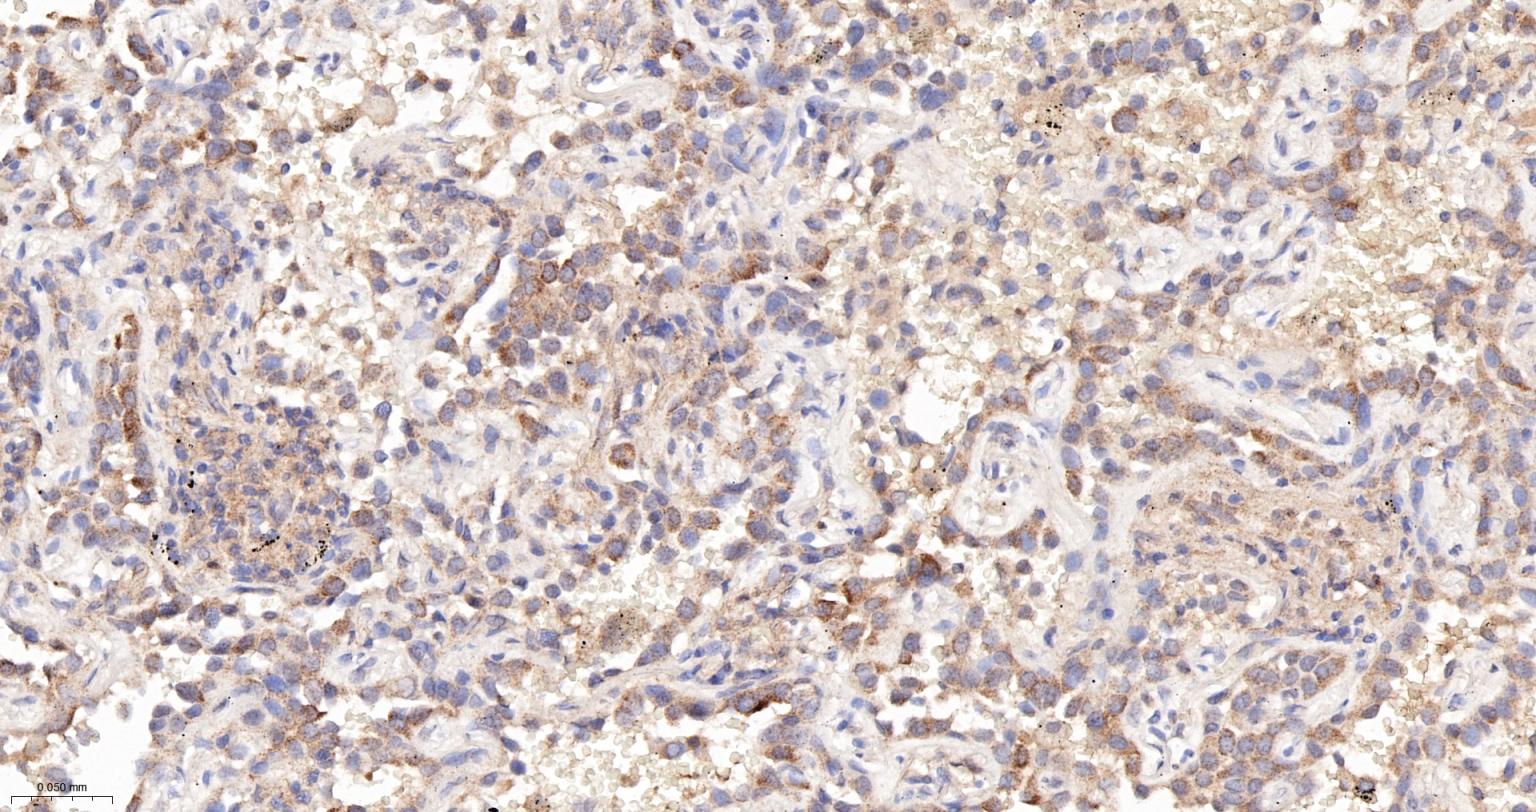

Paraformaldehyde-fixed, paraffin embedded Human Prostate Cancer; Antigen retrieval by boiling in sodium citrate buffer (pH6.0) for 15 min; The section was incubated with PTEN Monoclonal Antibody, Unconjugated (bsm-52369R) at 1:200 overnight at 4°C, followed by conjugation to the bs-0295G-HRP and DAB (C-0010) staining.